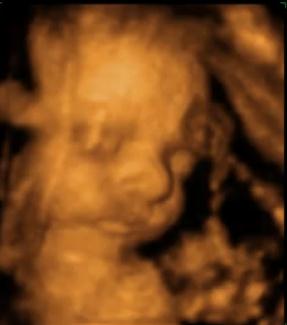

Видео:Видете го вашето бебе на 3D ултразвук

Помина времето кога можевте да го видите вашето бебе, на обична ултразвук снимка. Со новата 3Д ултразвук технологија, ќе можете да го следите секој чекор на вашето бебе. Но колку […]